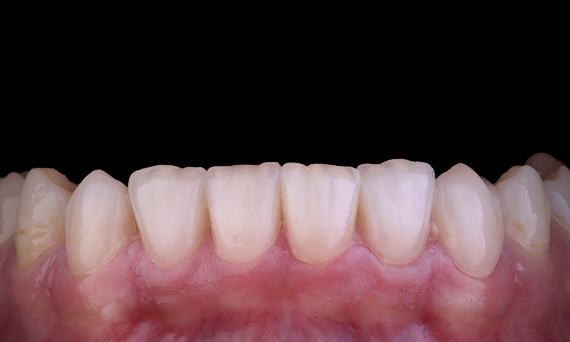

This patient presented with a broken restoration on tooth 46 distal-occlusal aspect. The tooth’s existing restoration extended very deep and close to the pulpal chamber. Given the large size of the restoration, it was highly likely that if we simply replaced the restoration with another direct restoration, the result would be the same, with the restoration breaking under the occlusal loads the tooth and restoration are subjected to. So an indirect option was recommended for the tooth. As the mesial third of the tooth was largely unaffected with substantial sound tooth structure remaining, we could preserve it and be minimally invasive by restoring the tooth with an indirect restoration using the CEREC system

Dr Sahil Soni, Queensland, Australia